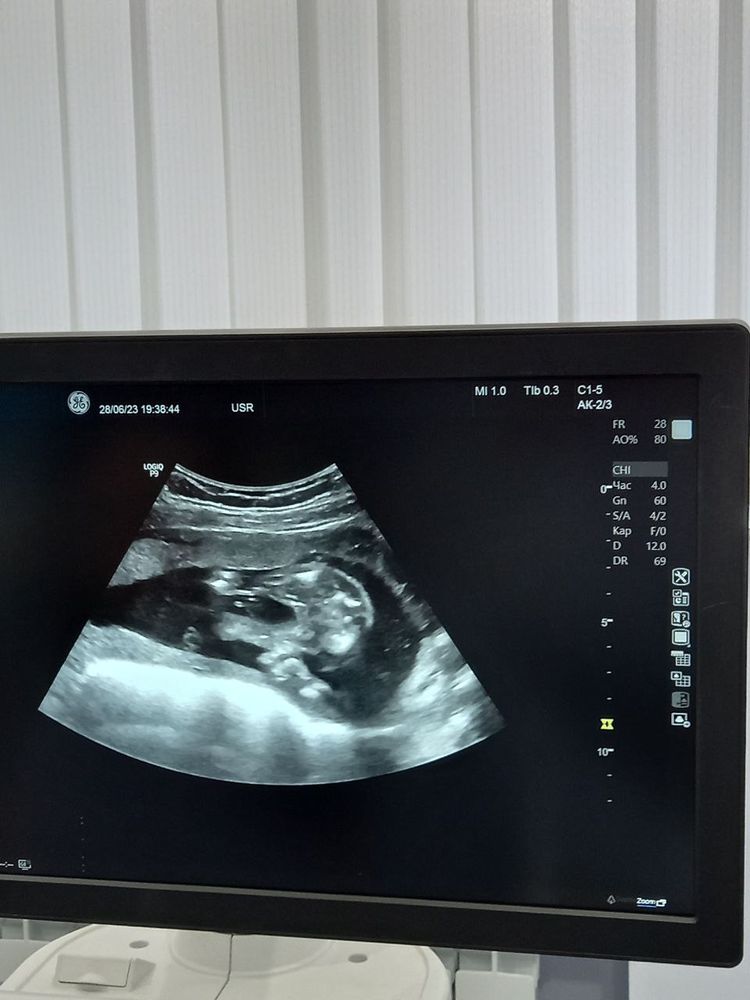

Девчонки, сегодня была на узи. Сказали, что 100% девчонка. Посмотрите, кто разбирается, пожалуйста)

Девчонки, сегодня была на узи. Сказали, что 100% девчонка. Посмотрите, кто разбирается, пожалуйста)

Разбирается ваш врач УЗИ. Здесь по таким статичным и непонятным снимкам вам к о чего скажет?

Я на Вашем фото даже не понимаю где ребёнок)))))

А так, на этом сроке, думаю, врач вряд ли ошибся